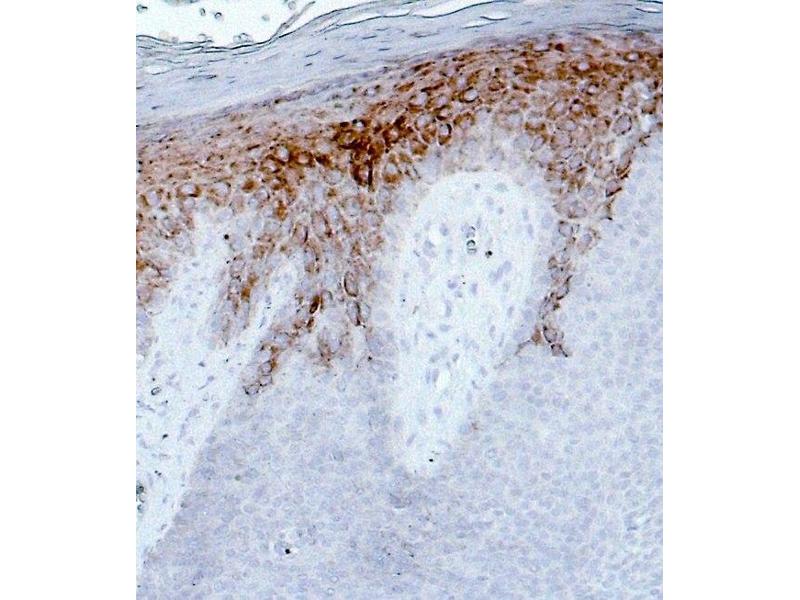

This 豚鼠 多克隆 antibody specifically detects KRT16 in IHC 和 WB. It exhibits reactivity toward 人.

Immunohistochemistry (IHC), Western Blotting (WB)

Synthetic peptide of human keratin K16 (formerly also designated cytokeratin 16, C-KE QSS SSF SQG QSS)

Dilution for IHC: 1:100 - 1:200

MW 48,000 (pI 5.1) intermediate filament polypeptide, keratin K16, detected by immunohistochemistry in psoriatic skin, in the rete ridges of foot sole epidermis, in tongue, esophagus, exocervix and in squamous cell carcinoma of skin, tongue and cervix. In the hair follicle, staining was restricted to the outer root sheath. Completely non-reactive were cells of non-stratified epithelia (e.g. liver, colon).